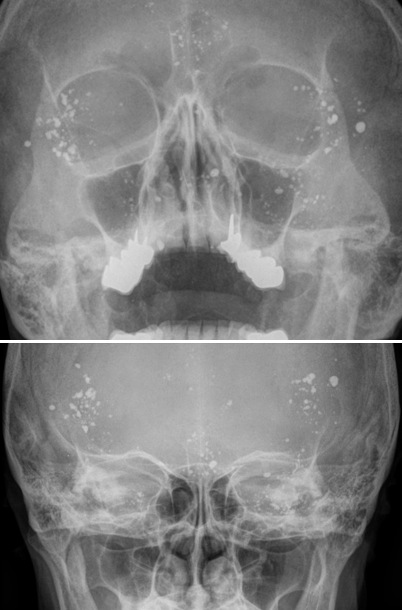

Figure 1 for case Lipiodol droplets after myelogram

Figure 1

Figure 2 for case Lipiodol droplets after myelogram

Figure 2